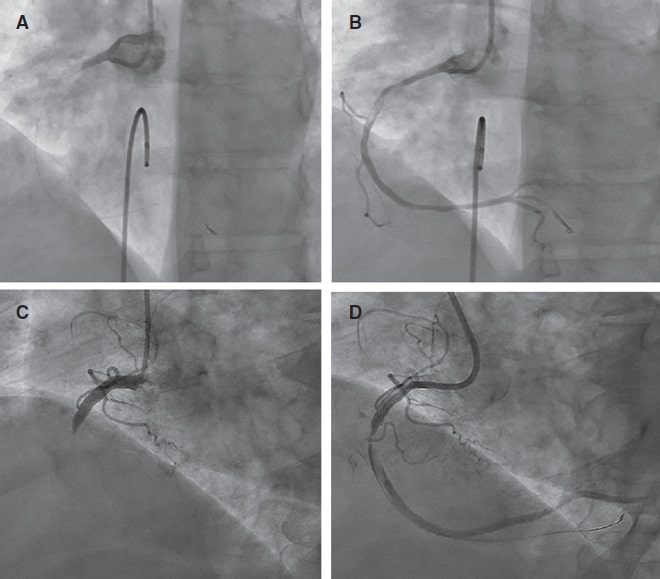

No significant differences in terms of final stent expansion, minimal stent area, or final residual stenosis were observed between groups (table 2, figure S2). Angiographic, procedural, and clinical success rates exceeded 90% (considering < 30% residual percent diameter stenosis) in both age groups and did not differ by technique (table 2, figure 1).

Figure 1. Angiographic, procedural, and clinical success of each technique. Angiographic success defined as final Thrombolysis in Myocardial Infarction grade-3 flow with < 30% residual percent diameter stenosis. Procedural success was considered angiographic success without major perioperative complications. Clinical success was defined as procedural success without in-hospital major adverse cardiovascular events.